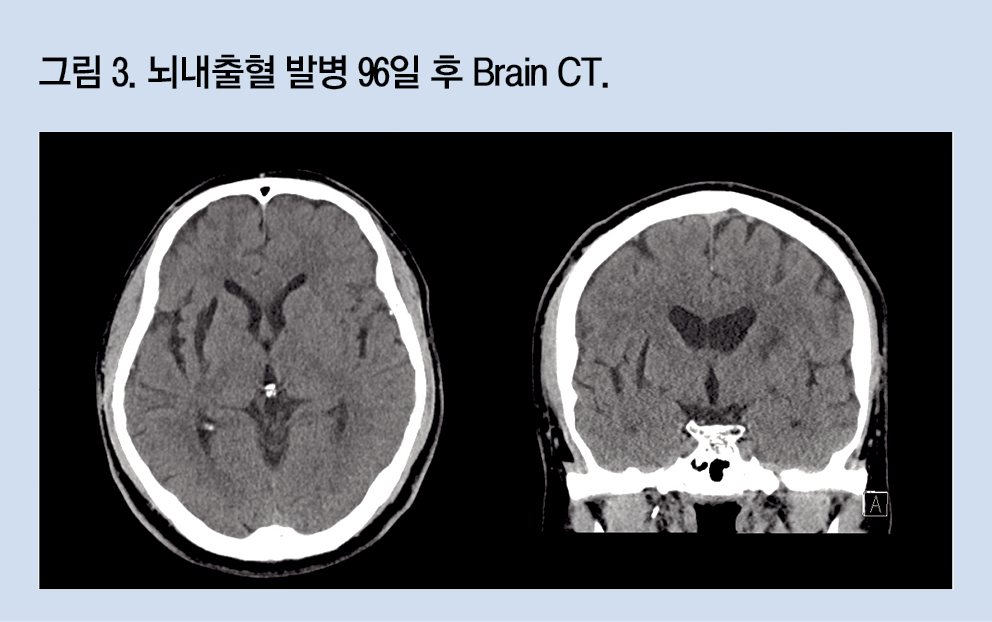

다행히 환자는 계획된 치료를 잘 따라 주었다. 그 결과 좌측 안면 마비와 상하지 근력 저하가 서서히 회복되고, 화학합성약물 복용 없이 혈압이 안정적으로 잘 유지됐다. 발병 약 3개월 후 시행한 brain CT 검사에서 혈종 및 부종이 모두 호전된 것으로 관찰됐다(그림 3). 치료 5개월 후 BMI 22.5 ㎏/㎡, Cholesterol, total 259 ㎎/dL, Triglyceride 103 ㎎/dL 등 다른 검사 결과도 크게 회복됐다. 환자는 ‘편안한, 건강한 병원 방문이었습니다’라는 말로 치료 과정을 요약했다.